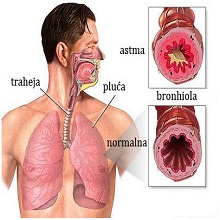

Астма је хронична опструктивна запаљенска болест дисајних путева која узрокује проблеме при дисању. Карактеришу је јак имунолошки одговор и хронична упала трахеобронхијалног стабла. |

| Најчешће хронично респираторно обољење код деце предшколског и школског узраста је астма. Два пута чешће јавља код дечака него код девојчица, али се у периоду адолесценције овај однос изједначава. Продужен експиријум и свирање у грудима указују на астму. |